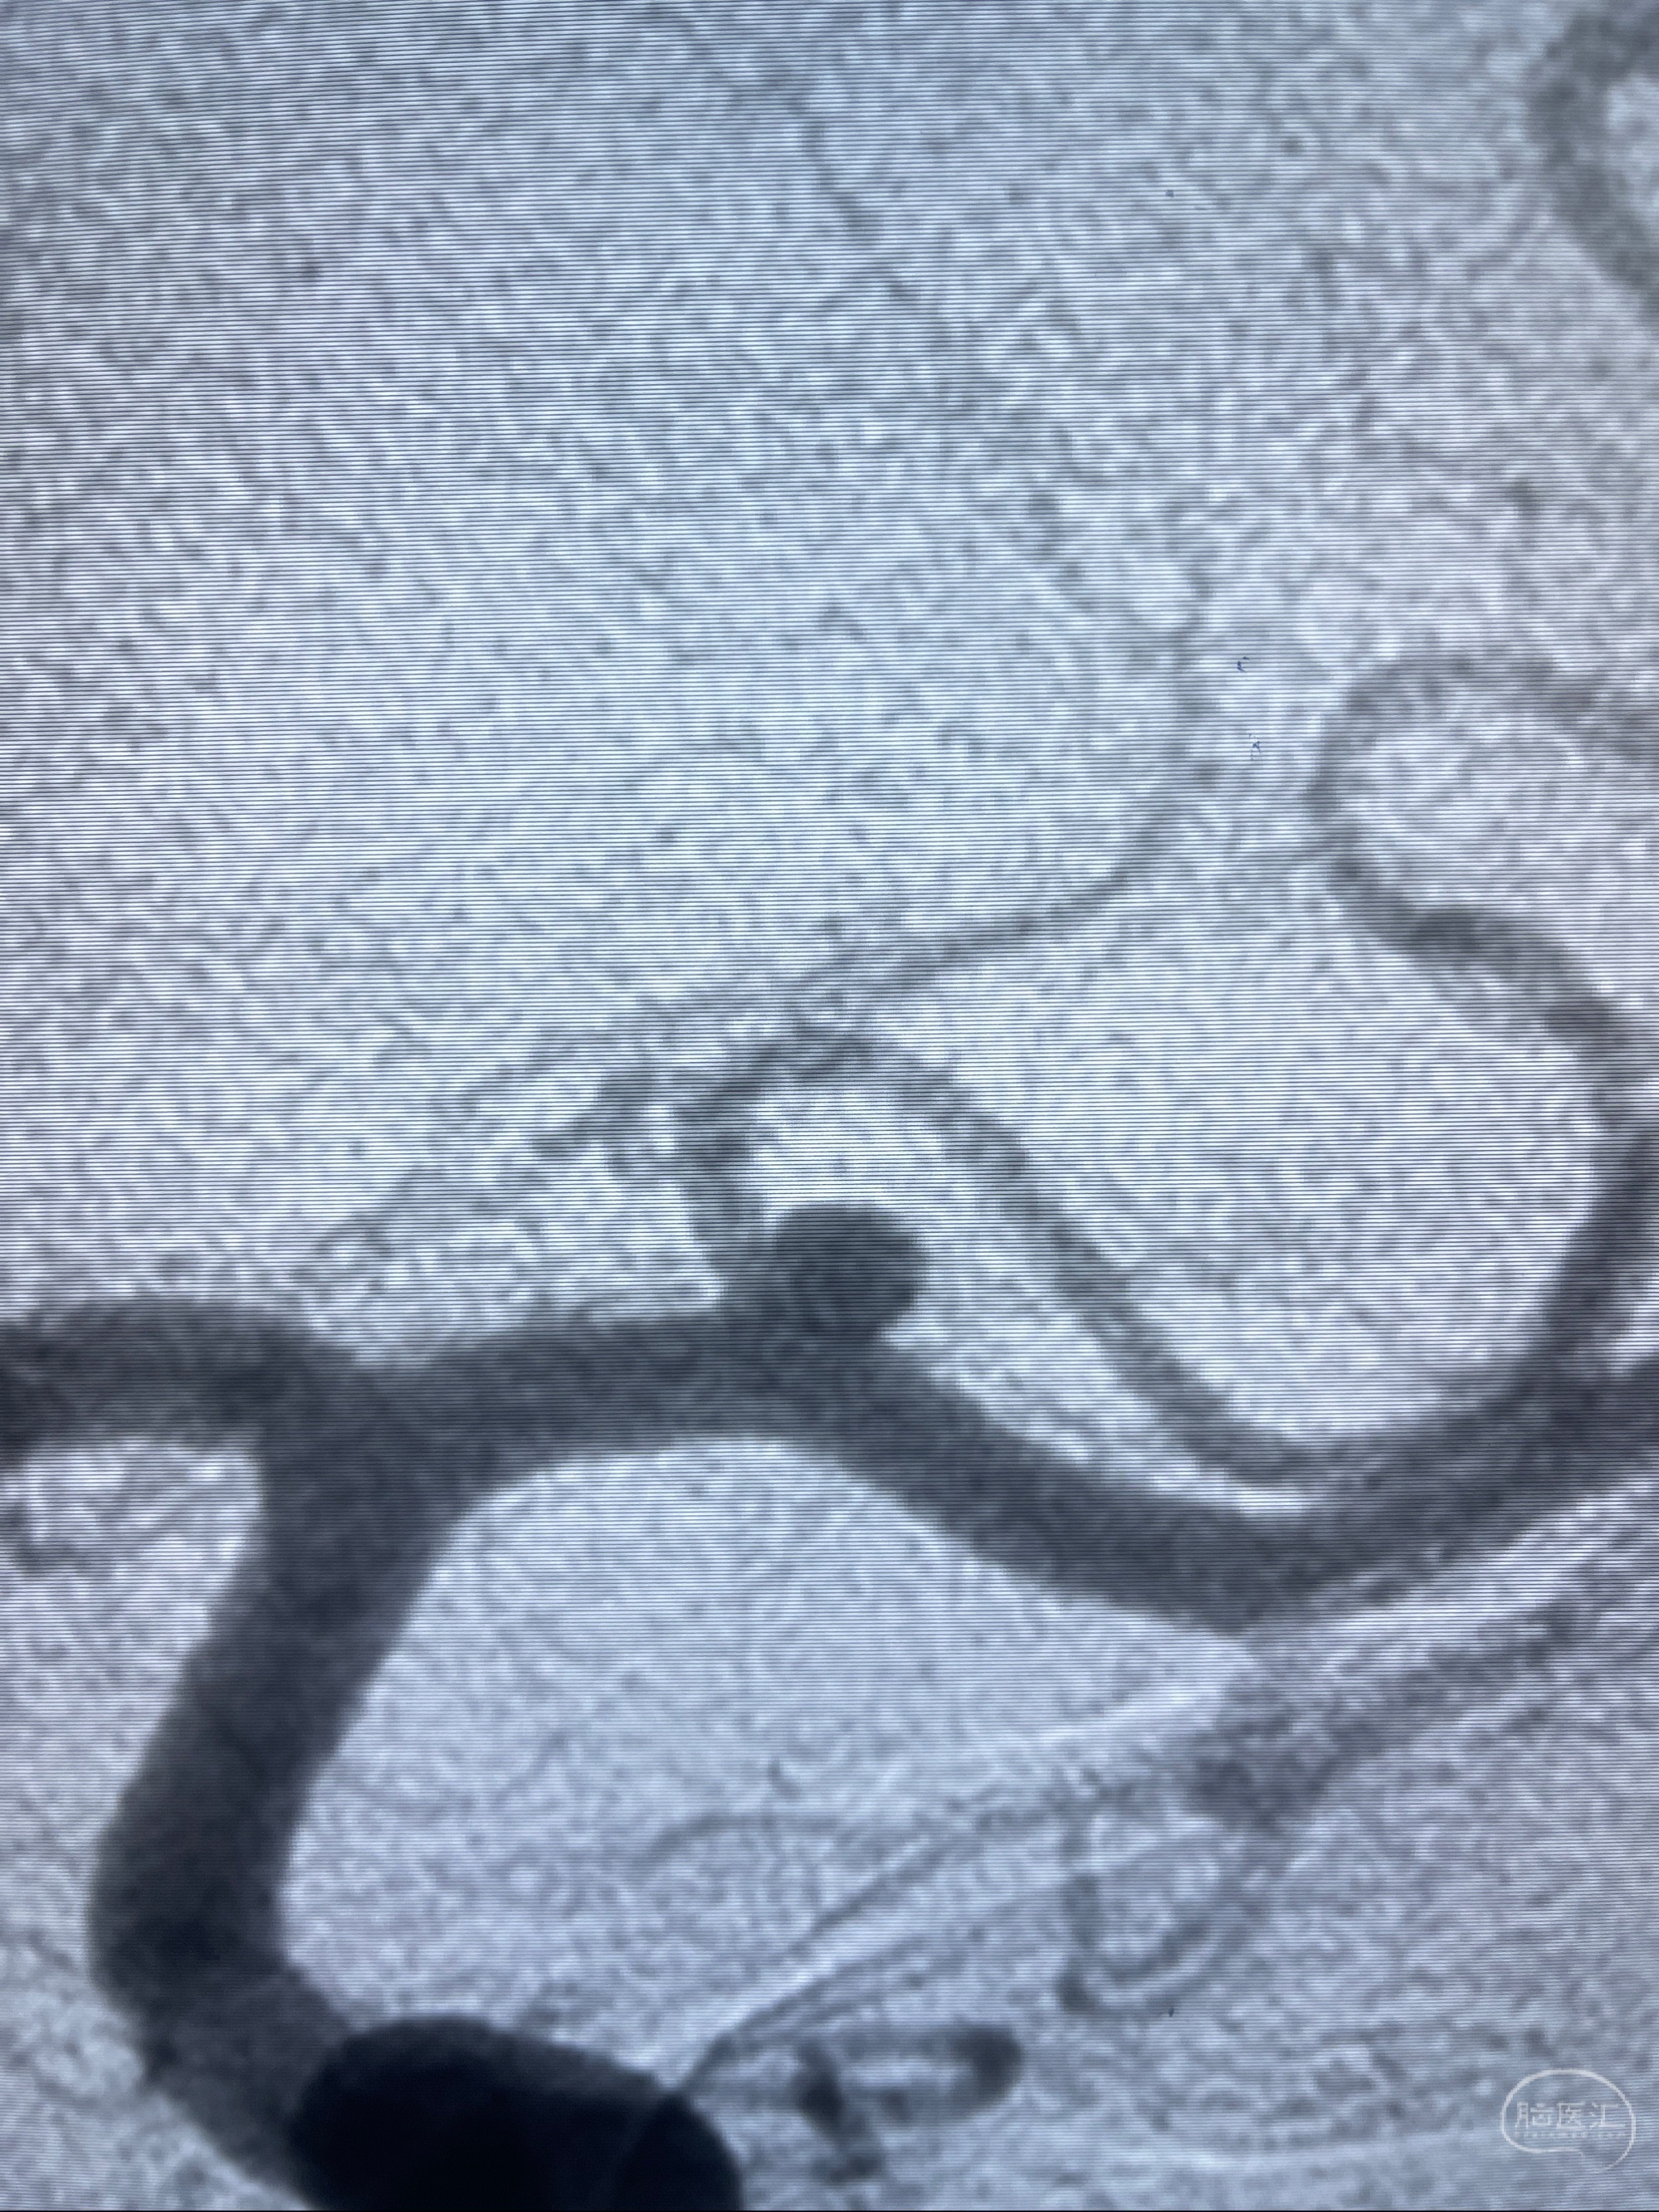

2023-08-14DSA:

左侧大脑中动脉动脉瘤,约2.6-2.8-3.4-2mm大小(瘤颈部、瘤体部、瘤高)

1.左侧大脑中动脉动脉瘤,约2.6-2.8-3.4-2mm大小(瘤颈部、瘤体部、瘤高)